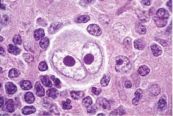

U mềm lây là bệnh da liễu truyền nhiễm do một loại vi khuẩn gây ra. Cùng eLib.VN tìm hiểu ngay nguyên nhân, triệu chứng sớm nhất để kịp thời điều trị hiệu quả bệnh với bài viết dưới đây nhé!

U mạch máu phần lớn xảy ra ở trẻ dưới 1 tuổi. Ban đầu có thể bé sẽ có những vùng da màu đỏ, thường là trên mặt, ngực hoặc lưng. Qua thời gian, những phần bị đỏ này phát triển thành những chỗ lồi trên da. U mạch máu sẽ trở nên phẳng dần và biến mất. Cùng eLib.VN tìm hiểu bài viết dưới đây để hiểu rõ hơn về bệnh lý này nhé!

Bệnh U hạt (hay còn gọi là bệnh Sarcoidosis) là tình trạng sự tăng trưởng quá mức của các tế bào viêm ở các bộ phận khác nhau của cơ thể, dẫn đến các bệnh viêm cơ quan, thường gặp nhất là ở phổi, hạch bạch huyết, mắt và da. Cùng eLib.VN tìm hiểu bài viết dưới đây để hiểu rõ hơn về bệnh lý này nhé!